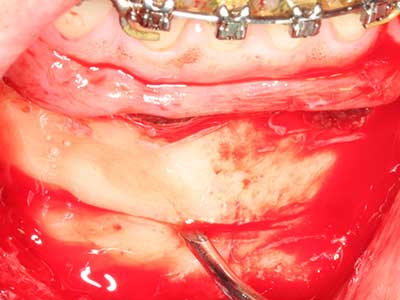

Bei der Knochenblockentnahme zeigen sich weitere Vorteile für die Piezochirurgie: Neben der bereits beschriebenen hohen Präzision bei der Osteotomie stellt sich gerade die Verwendung der dünnen Sägespitzen als besonders materialschonend heraus. Bei der Verwendung insbesondere von Lindemannfräsen sind mit deutlich höheren Entnahmeverlusten durch die dickere Instrumentenspitze zu rechnen (Lakshmiganthan, Gokulanathan et al. 2012). Die insbesondere bei retromolar entnommenen Blocktransplantaten notwendige basale Abtrennung wird durch speziell hierfür vorgesehene rechtwinklige Sägen erleichtert, so dass die Piezochirurgie als präzises, übersichtliches und sicheres Verfahren zur retromolaren Knochenblockgewinnung angesehen wird (Happe 2007) (Abb. 1-12).